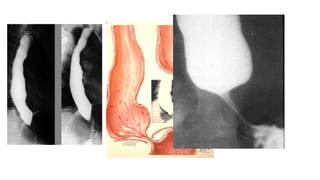

Multiple smooth tapered concentric narrowing of the cervical esophagus in keeping with esophageal webs.

• Plummer-Vinson syndrome

with jet effect